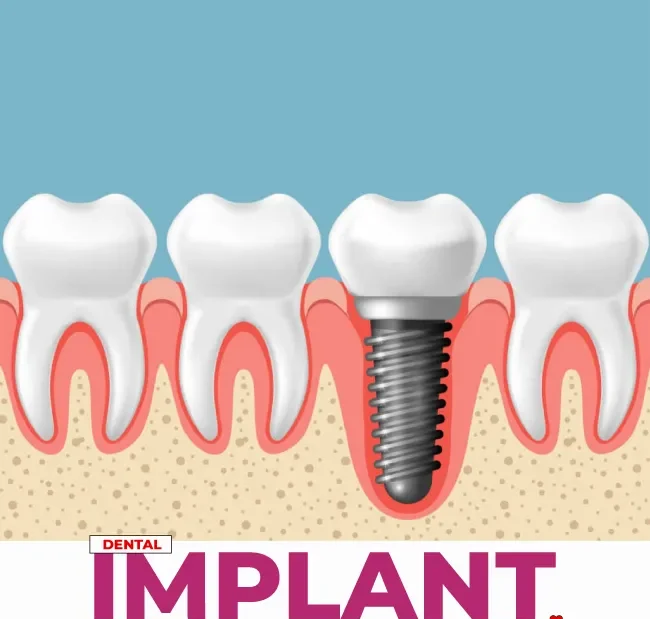

What is Dental Implant?

Dental implant is advanced dental procedures that involve the replacement of missing teeth by surgically implanting artificial tooth roots into the jawbone.

There are primarily two types of dental implants based on their design and placement:

- Endosteal Implants: These are mostly used implants placed directly on jawbone. They are typically screw-shaped or cylindrical in design. Endosteal implants are used for various tooth replacement options, such as single crowns, bridges, and dentures.

- Subperiosteal Implants: Subperiosteal implants are positioned on or above the jawbone but underneath the gum tissue. They consist of a metal framework that protrudes through the gums to support replacement teeth. Subperiosteal implants are less commonly used today but may be suitable for patients with minimal bone height.

- Implant Placement: During the surgical phase, the dental implant is placed into the jawbone. An incision is made in the gum to access the bone, and a hole is drilled to insert the implant. In some cases, a healing abutment may be attached to the implant at this stage.

- Healing Period (Osseointegration): Over the next few months, the jawbone heals and integrates with the implant. This process is known as osseointegration and is crucial for implant stability.

- Abutment Placement: Once the implant has fused with the bone, a small connector piece called an abutment is attached to the implant. The abutment protrudes through the gum and serves as the anchor for the final restoration.